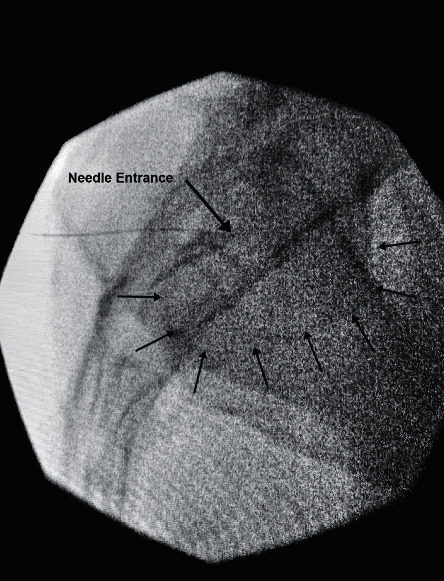

AP fluoroscopic view of the sacroiliac joint. The joint line is identified between the sacrum and ilium. Note the overlapping cortical margins that must be separated with oblique angulation.

• Apply 10-25 degrees of cephalad tilt so the inferior joint projects just above the superior pubic ramus; this separates posterior from anterior joint planes vertically

• Obtain an adjusted AP view (typically 5-20 degrees contralateral oblique) to superimpose the anterior and posterior joint margins at the caudal third

• Then rotate ipsilaterally to separate the joint lines horizontally — the medial silhouette usually represents the posterior (accessible) joint line

• Adjust obliquity until the inferior one-third of the medial joint line cortex is maximally crisp, indicating the beam is parallel to the posterior opening